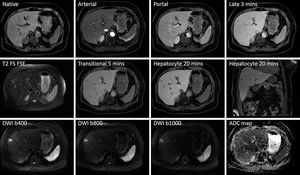

Gadoxetate Disodium–Enhanced (Primovist/Eovist) MR Imaging of small Liver metastasis. The combination of hepatospecific contrast agent with anatomical and functional imaging techniques can greatly increase the sensitivity and specificity of the examination. Images courtesy of Christos Tsiotsios.